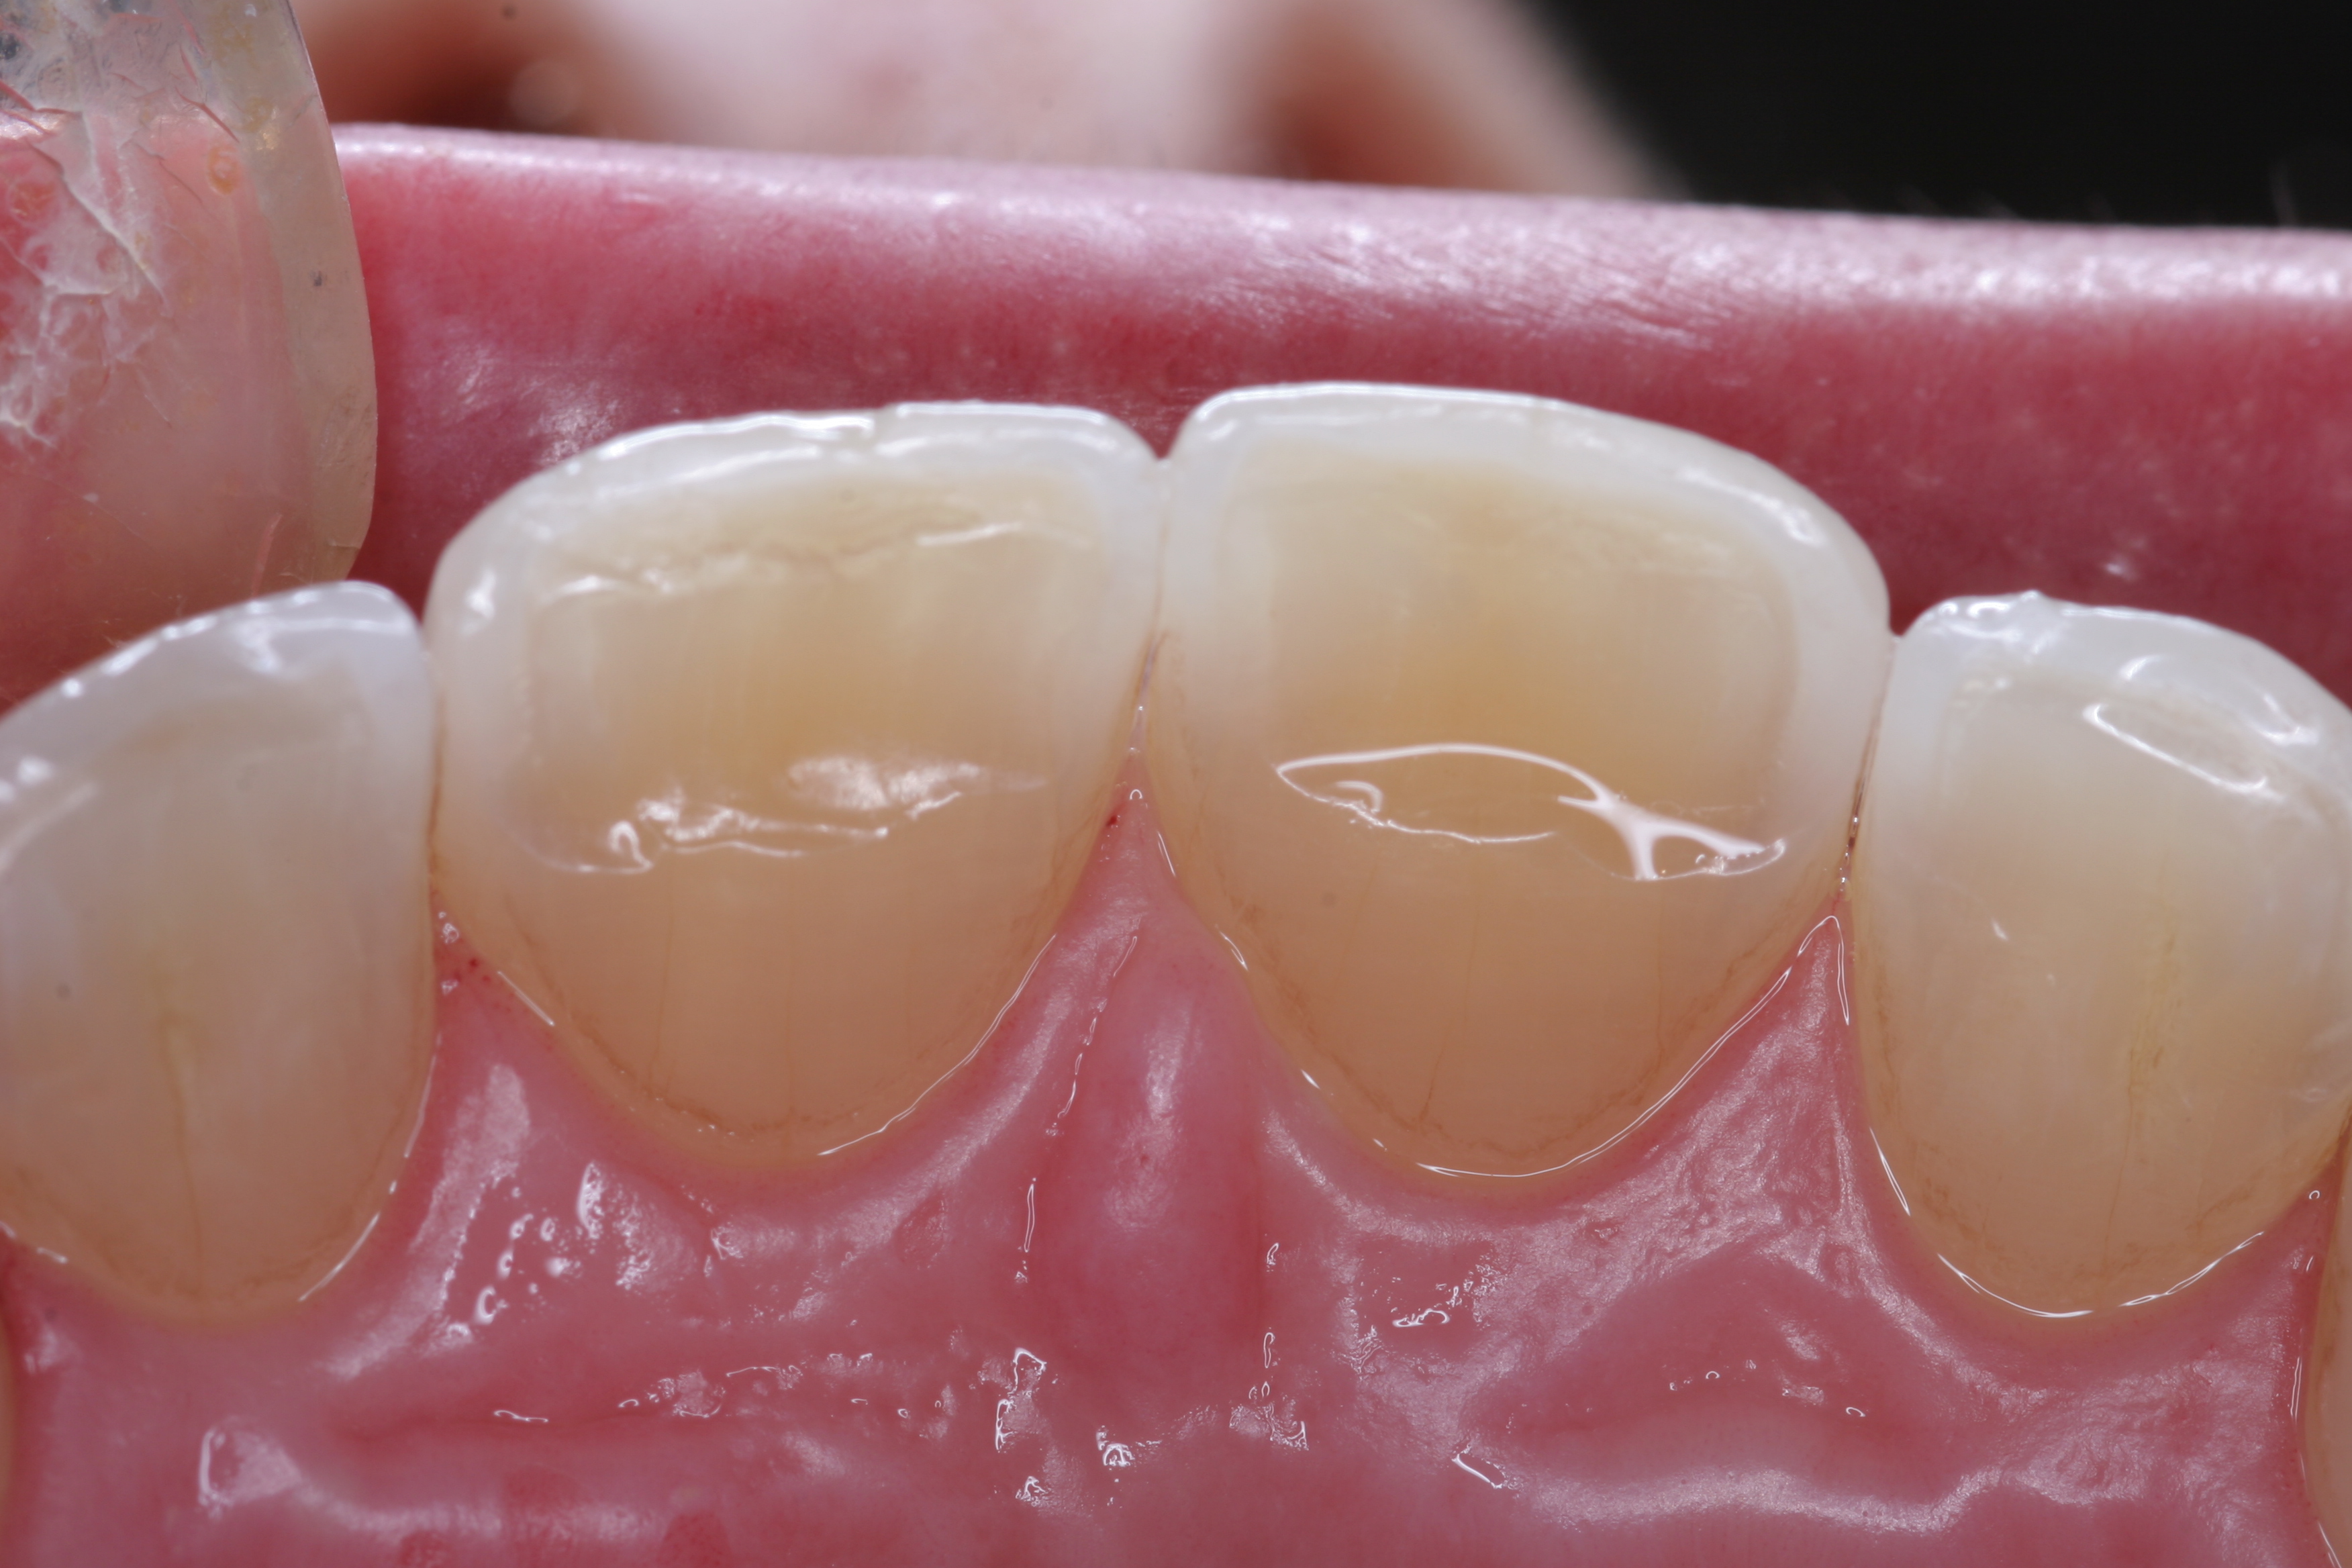

Once approved, impressions of the provisionals were taken so the laboratory could precisely copy the 3D position of the anterior teeth as successfully proven in the provisionals. The postoperative result and final functional photographs are shown in Figure 22 through Figure 29. Posterior treatment can now be completed in segments as necessary. Posterior morphology will be developed in harmony with the now corrected anterior contour and functional parameters. The fulfillment of the previously mentioned requirements of occlusal stability were evaluated and refined in the final restorations. The patient was placed in a posttreatment dual-arch B splint appliance to help manage any further parafunctional forces should they occur.

(22.) The final restorations, which reflect the changes modeled through the provisional phase.

Figure 22

(23.) The final restorations, which reflect the changes modeled through the provisional phase.

Figure 23

(24.) The final restorations, which reflect the changes modeled through the provisional phase.

Figure 24

(25.) The final restorations, which reflect the changes modeled through the provisional phase.

Figure 25

(26.) The final restorations, which reflect the changes modeled through the provisional phase.

Figure 26

(27.) The final restorations, which reflect the changes modeled through the provisional phase.

Figure 27

(28.) The final restorations, which reflect the changes modeled through the provisional phase.

Figure 28

(29.) The final restorations, which reflect the changes modeled through the provisional phase.

Figure 29